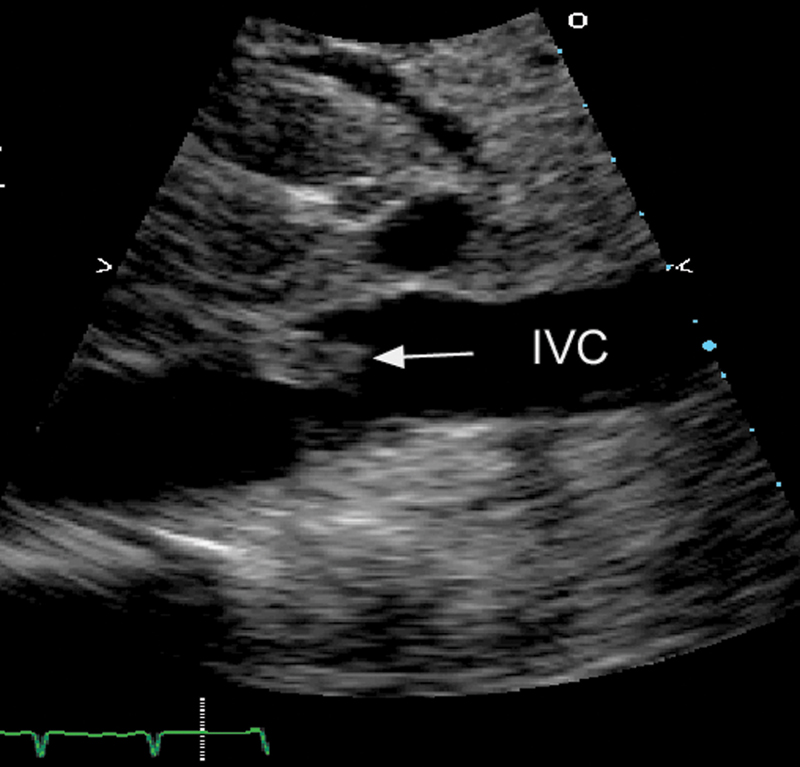

فحوصات تشخيصية لبعض امراض القلب والشرايين التاجية